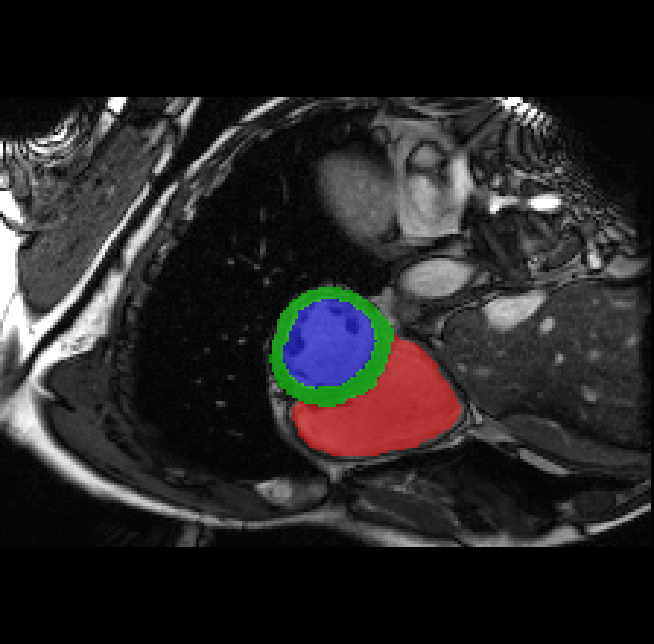

Table 2 presents an ablation study and compares SparseMamba-PCL with nine SOTA scribble-supervised methods across the three datasets. Out method achieves the highest Dice score across all the datasets, and the lowest (CHAOS) and second lowest (ACDC and MSCMRSeg) HD95 values, confirming its effectiveness in segmentation accuracy and boundary refinement. Baseline+SPOBE and Baseline+PCL improve upon the Baseline (SparseMamba), demonstrating the benefits of boundary-aware supervision and SAM-guided learning. Fig. 4 (l) compares the segmentation performance of SparseMamba-PCL with other scribble-supervised methods, showing smoother edges that precisely delineate object boundaries, unlike the jagged or blurred edges in other methods. The examples also demonstrate the consistent segmentation quality achieved by SparseMamba-PCL across ACDC, CHAOS, and MSCMRSeg, highlighting its adaptability across multiple medical domains. This adaptability and precise segmentation is crucial for accurate volumetric analysis and clinical decision-making, where even subtle boundary inaccuracies can lead to diagnostic errors. In summary, the SparseMamba-PCL architecture provides a consistent and robust improvement in segmentation metrics across diverse medical image datasets.

Refer to caption Refer to caption Refer to caption Refer to caption Refer to caption Refer to caption Refer to caption Refer to caption Refer to caption Refer to caption Refer to caption Refer to caption

(a) (b) (c) (d) (e) (f) (g) (h) (i) (j) (k) (l)

Figure 4: Qualitative comparison of weakly-supervised segmentation methods on ACDC, CHAOS, and MSCMRSeg datasets. (a) Input image, (b) ground truth, and segmentation results from (c) USTM [16], (d) Scribble2D5 [5], (e) CycleMix [26], (f) ShapePU [27], (g) S²ME [21], (h) ScribbleVC [12], (i) TDNet [30], (j) PacingPseudo [25], (k) Scribbleformer [13], and (l) SparseMamba-PCL are given.